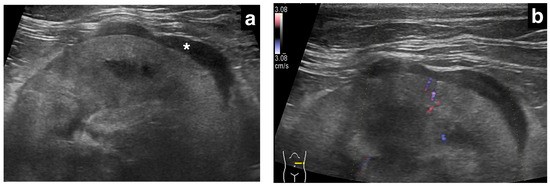

肾转移性肺癌的超声图像

超声检查共评估9个肾脏(双侧3例,左侧2例,右侧1例)。被膜下增厚最大厚度1.0-13.2 mm(中位数3.0 mm),其中原发性肾细胞癌病例增厚最显著(13.2 mm),转移性癌均小于5 mm。分布特征上,8个转移性癌肾脏表现为局灶性、均匀低回声增厚,1个原发性肾癌肾脏呈环周性、不均匀混合回声增厚。肾皮质边缘和包膜边缘各见5例光滑、4例不规则。5个肾脏行彩色多普勒检查,2例增厚病灶内可见血流信号,仅1例双侧出现肾周积液。

肾实质异常见于7个肾脏,表现为弥漫性高回声(3例)或局灶性高回声(4例),其中3例高回声区内可见低回声条纹,多位于被膜下增厚区域下方。皮髓质分界不清7例,完全消失1例。2个肾脏可见肾盂轻度扩张,2个肾脏存在多发小钙化灶,1例可见肾皮质囊肿,2例转移性癌肾脏可见高回声结节。肾脏长径3.4-6.0 cm(中位数4.1 cm),4个转移性癌肾脏出现肾肿大,未见肾缩小。

本研究报道了猫原发性或转移性癌可导致肾脏低回声被膜下增厚。研究发现,转移性癌(主要来源于肺腺癌)多表现为局灶性、均匀低回声增厚(厚度<5 mm),而原发性肾癌可表现为环周性、不均匀混合回声增厚。组织病理学证实,增厚层内可见肿瘤细胞浸润或坏死组织,提示该征象可能源于肿瘤细胞沿肾被膜下淋巴系统播散。